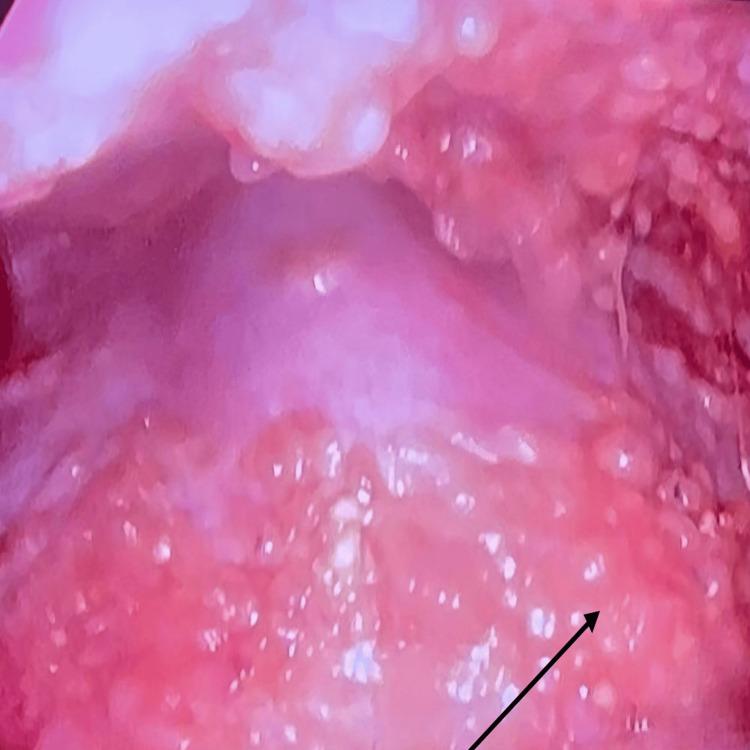

原发性肺淋巴瘤(PPL)是一种累及肺部的罕见疾病,其特征为淋巴样细胞的异常克隆性生长。PPL患者可能无症状,或表现出如咳嗽、发热、胸部不适和呼吸急促等模糊的临床症状。一些患者可能还存在潜在的免疫抑制或自身免疫性疾病。在流行地区,结核病更为常见且发病率更高,PPL常常会被误诊为结核病。此外,它们有共同的症状,如咳嗽、发热、疲劳、不明原因的体重减轻,且好发于上叶。因此,将PPL与其他常见肺部疾病进行鉴别诊断对于早期诊断和治疗至关重要。一般来说,小活检样本对于精确诊断和及时治疗必不可少。治疗选择包括化疗、放疗、免疫治疗和手术干预。在此,我们概述了一例最初表现为黑棘皮病,因呼吸道症状、胸腔积液和纵隔淋巴结肿大前来就诊的病例,最初被认为是结核性胸腔积液。除了临床放射学和实验室分析外,胸腔镜引导下活检和组织病理学检查为进一步诊断指明了方向。患者开始接受R-CHOP方案化疗。该病例表明,对于与弥漫性大B细胞淋巴瘤相关的副肿瘤综合征,需要多学科视角来进行明确和快速的诊断及管理。该讨论还强调了对副肿瘤综合征进行全面评估的必要性,因为它们在疾病的早期诊断和识别复发方面至关重要。